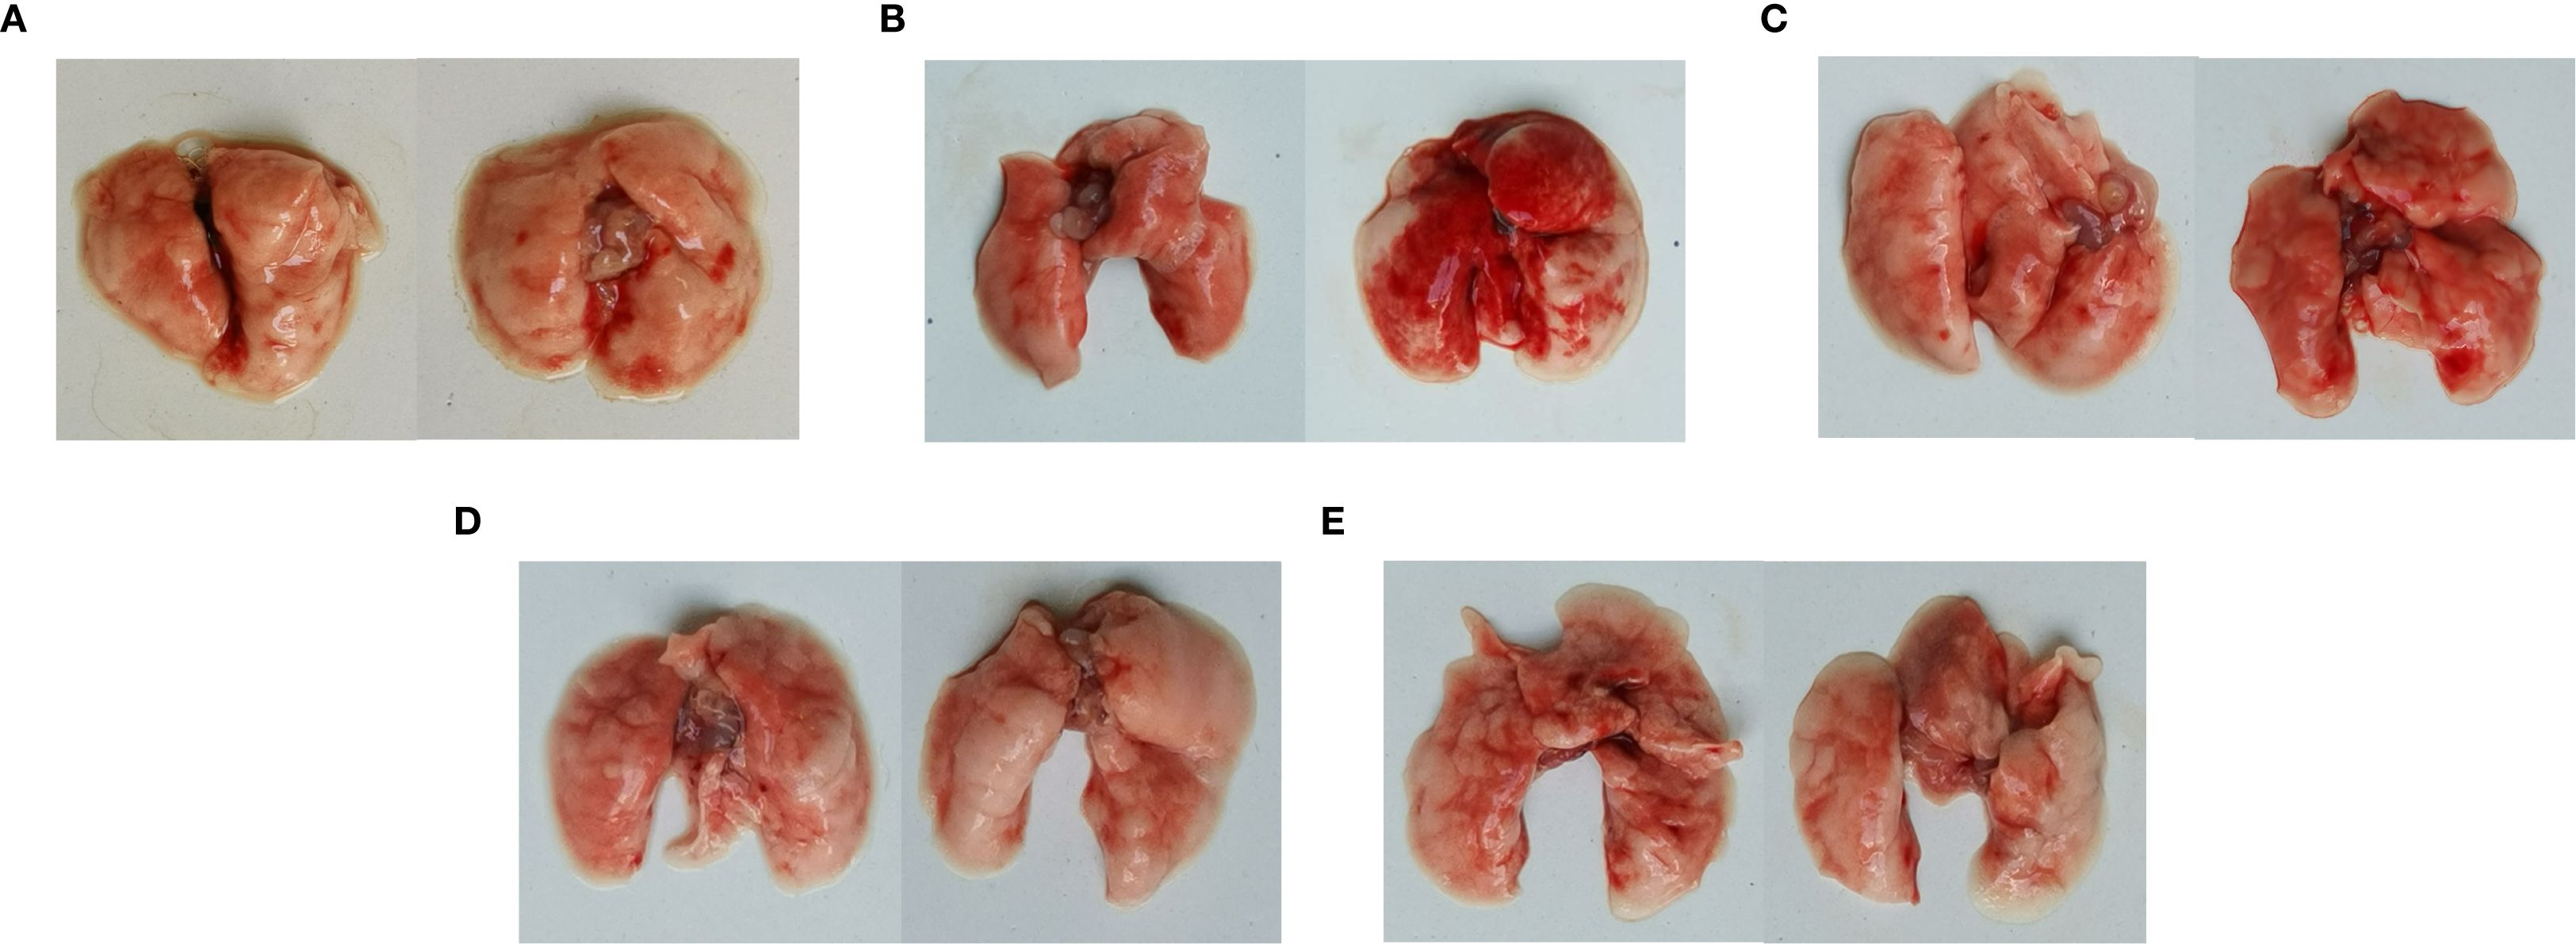

Postmortem, diffuse hemorrhagic lungs were observed in the mice with C. psittaci infection alone, while enlarged lung size was evident in the mice with E. faecalis infection (Figure 7). For C. psittaci/E. faecalis group and the C. psittaci+E. faecalis group, atrophy, viscous exudation, and diffuse hemorrhage characterized severe lesions, while fibrinous consolidation developed in the C. psittaci+E. faecalis group (Figure 7D).

Figure 7. Lung lesions after coinfection with Chlamydia psittaci and Enterococcus faecalis in mice. (A) Control group, (B) C. psittaci alone group, (C) E. faecalis alone group, (D) C. psittaci+E. faecalis group, and (E) C. psittaci/E. faecalis group.